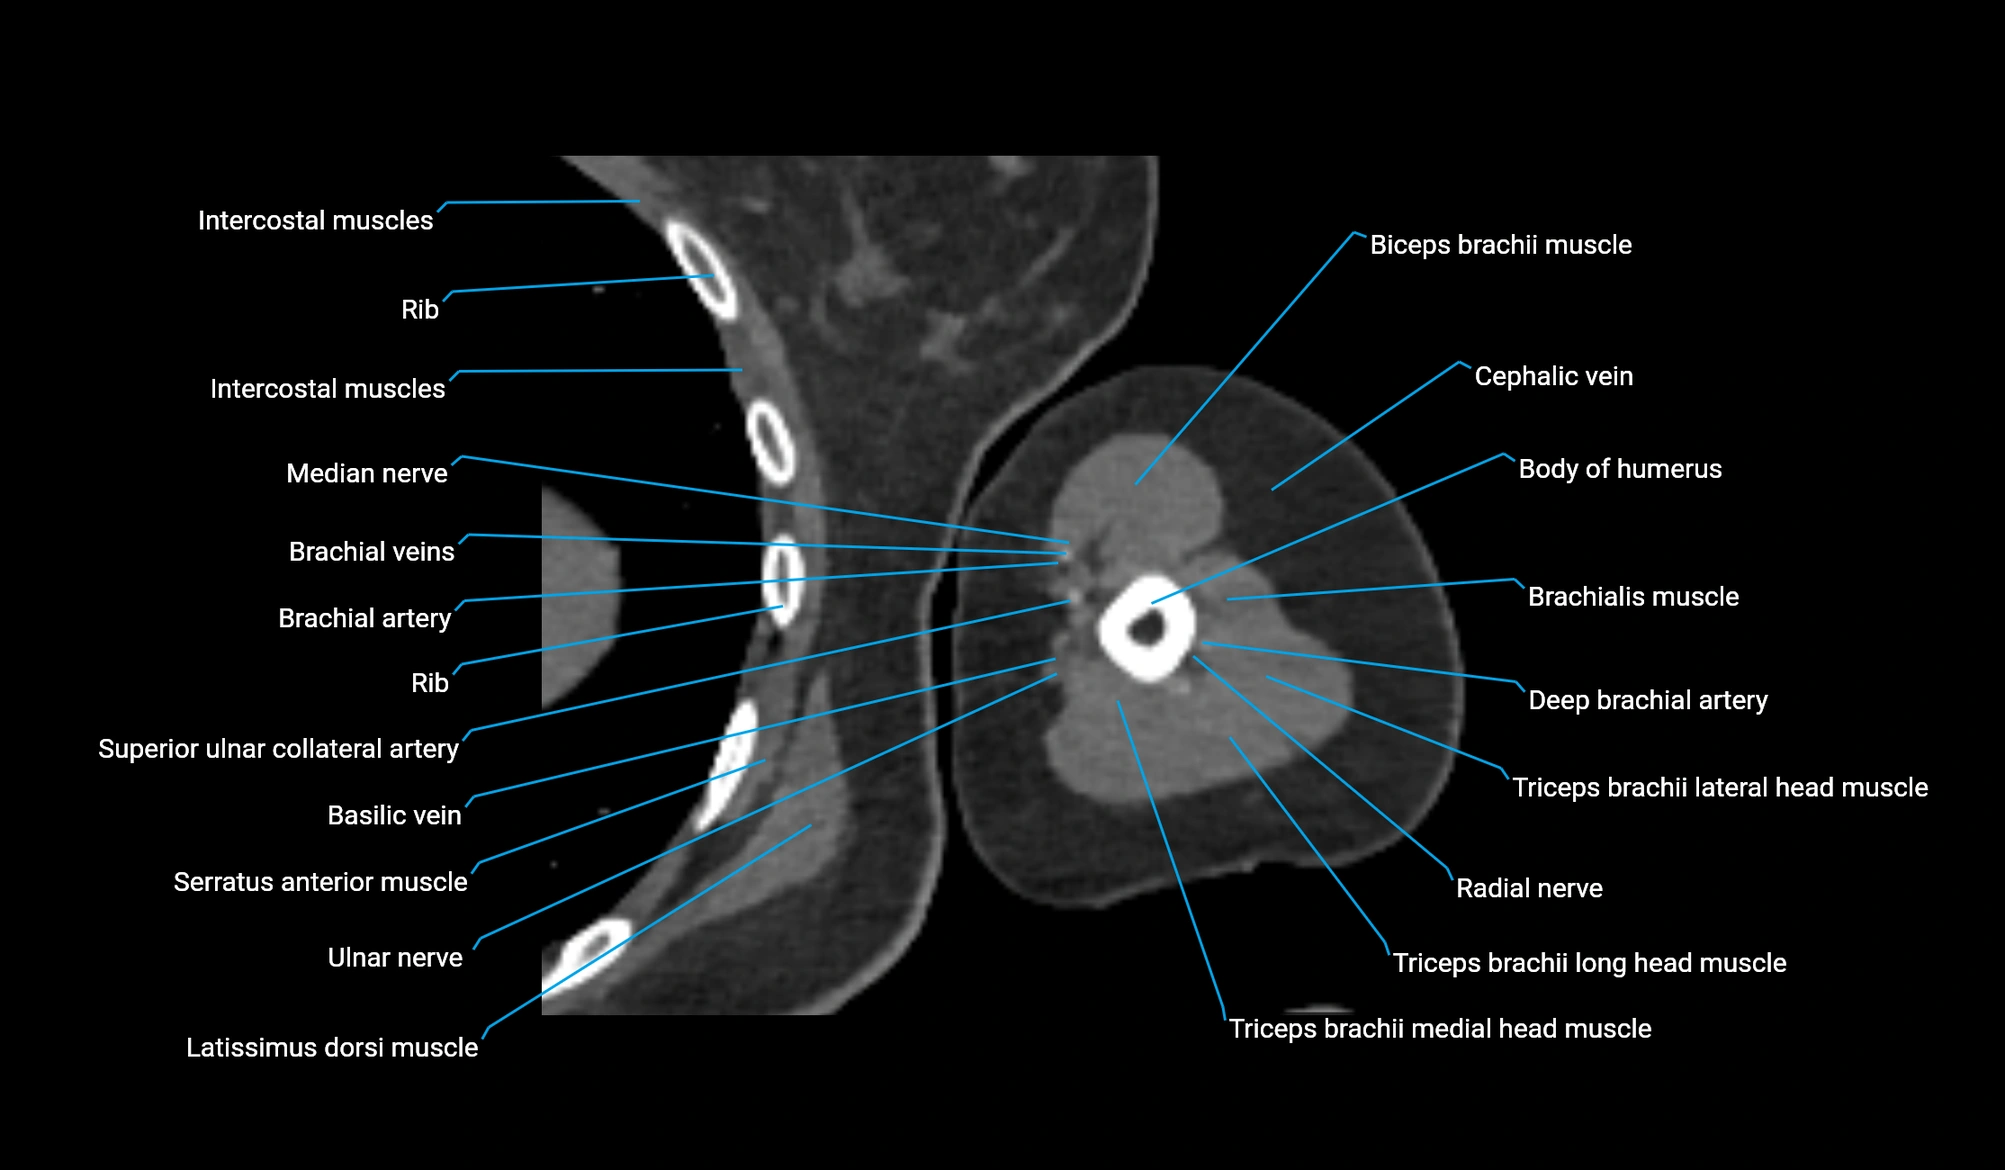

CT image